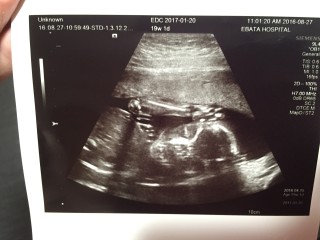

写真:19w1d:なんなさん:女の子

お腹の子供は標準の大きさで、出血もなく、先生には順調と言われました! このまま、何事も無く成長してくれますように。

1ヶ月ぶりの検診で、つわりも胎動も感じなくて、お腹の中で死んでしまってたら…ってすごく不安だったのですが、私の心配とはよそに、ちゃんとすくすく育っていてくれました(;▽;)!! 動いてるのを見た瞬間思わず涙が(;_;) 以前もかわいかったけど、肉付きがよくなって更にかわいいです。 口をぱくぱくさせて羊水を飲んでました。 性別は体位の問題でまだわからなかったので、また1ヶ月後のお楽しみ! 身長は24cmでした。 胎動らしきものも感じ始めたので、たくさんコミュニケーションを取っていこうと思います! 上の方に写っているのが胎盤です(*?*)

BPD4.40cm

FL2.73cm

258gでした!